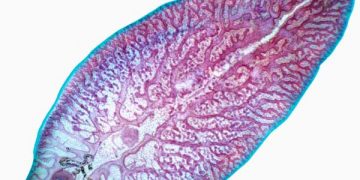

Yaprak Kelebeği, Fasciola hepatica